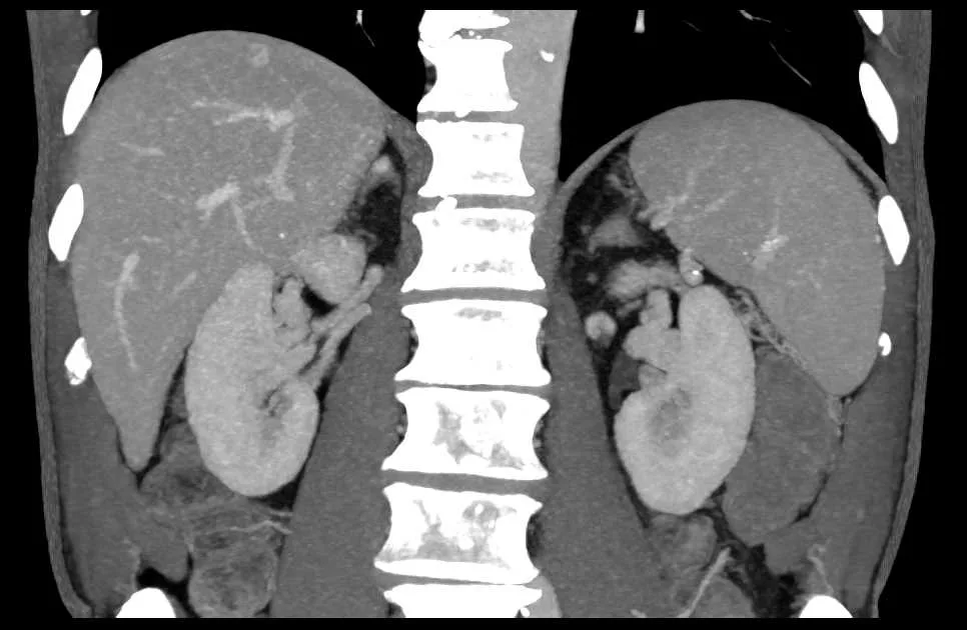

Так вот исходя из этого, надо понимать, что не менее 95% случаев повышенного давления - это так называемая "эссенциальная артериальная гипертензия". Которую нельзя свести к каким-то другим болезням. И лишь 5% случаев стабильно повышенного АД - это другие болезни, чаще эндокринные или заболевания почек, или апноэ сна. Как соотносятся по частоте причины вторичной артериальной гипертензии - видно из рисунка ниже:

Среди болезней почек, которые чаще всего приводят к вторичной гипертонии, упомяну гломерулонефрит, поликистоз почек и атеросклероз почечных артерий.